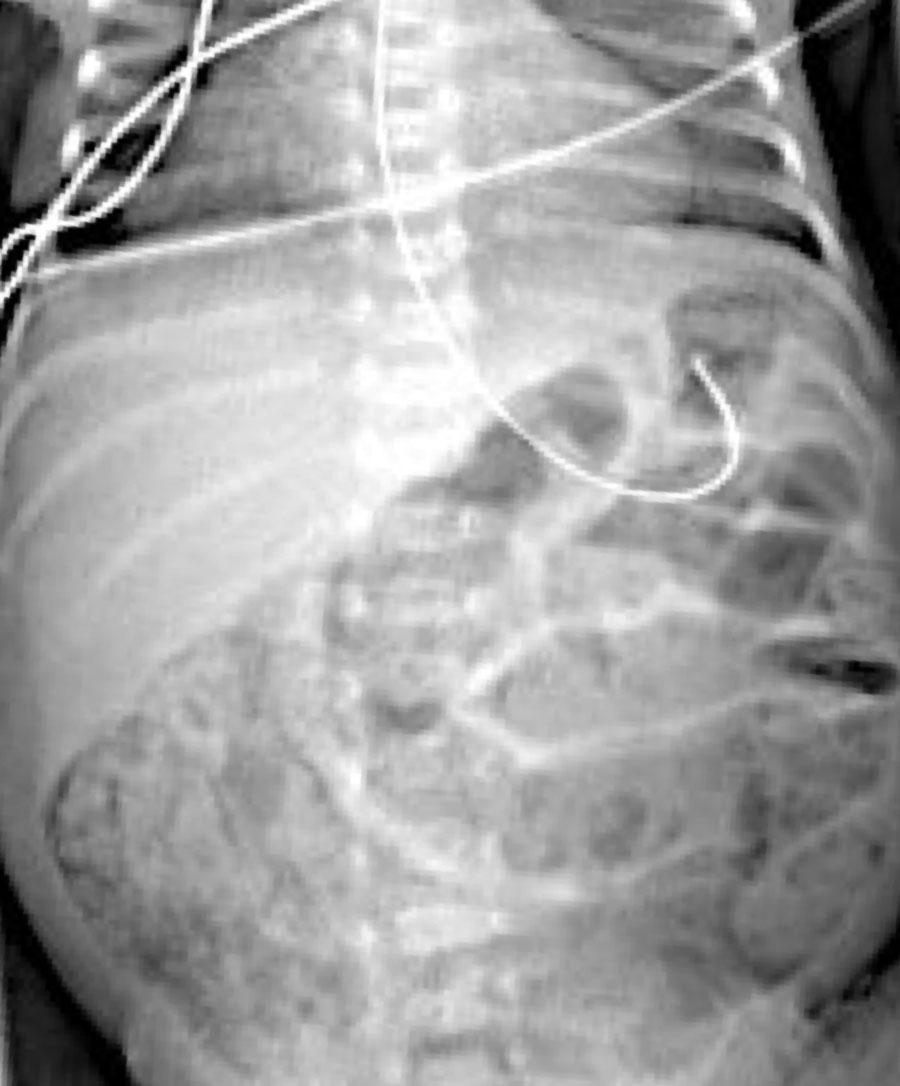

Đây là hình ảnh của một trẻ sơ sinh phát triển viêm ruột hoại tử.

Ở giai đoạn sớm này, X-quang chỉ cho thấy hình ảnh giãn ruột không đặc hiệu.

Ở giai đoạn này, không thể xác lập chẩn đoán.